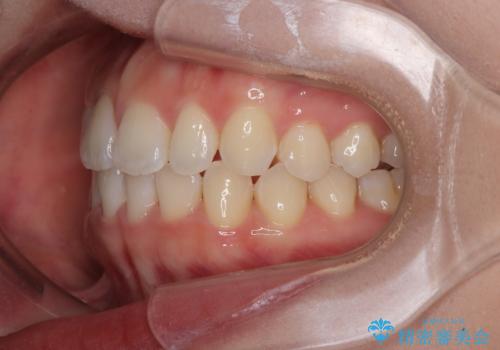

目立ちにくい表側装置で1年完了!狭いアーチを側方拡大し前歯のデコボコを整えた症例

- 前歯のデコボコが気になるでのことで来院された患者様です。

歯列アーチが狭くスペース不足により前歯がデコボコしている状態でした。見た目を改善しつつ、前歯を前方に突出させず、自然な笑顔を目指したいというご希望でした。